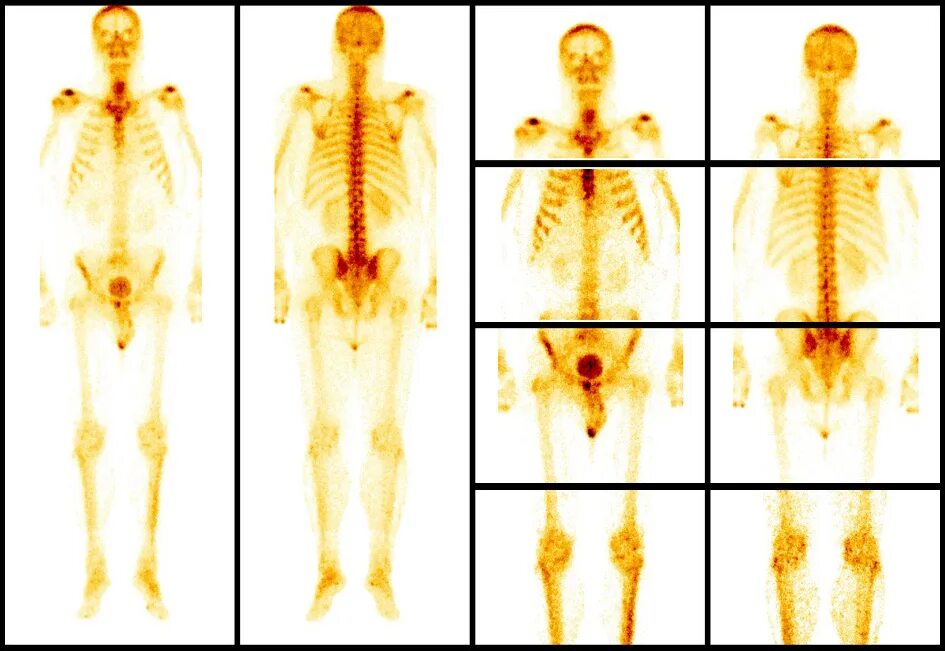

Как называется исследование костей